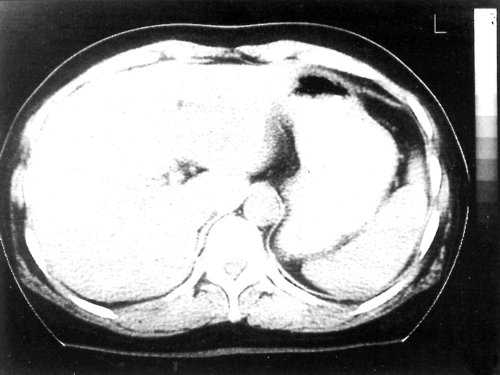

Рис. 2. КТ печени.

а) До контрастирования - в левой доле печени видно большое образование округлой формы.